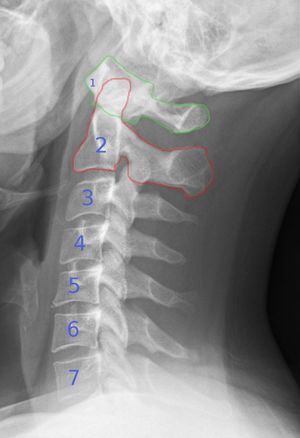

C-Spine X-Ray

Lateral View

- Alignment

- Disruption in the anterior, posterior, or spinolaminal lines

- Bones

- Obvious fracture

- Disruption of ring of C1

- Double facet sign indicates fractured articular facet

- Loss of vertebral height

- Cartilage

- Intervertebral disc space height and length should be uniform

- Narrowing: disc herniation or adjacent vertebral fracture

- Widening: posterior ligamentous injury

- Soft tissue

- Widening of the prevertebral soft tissue suggests fracture